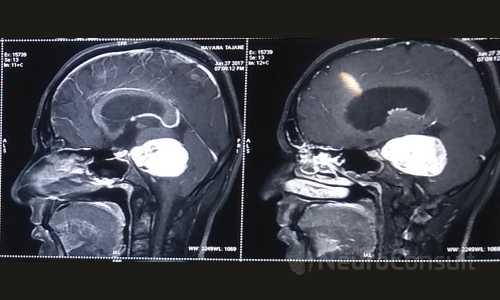

My Cases Studies & Work